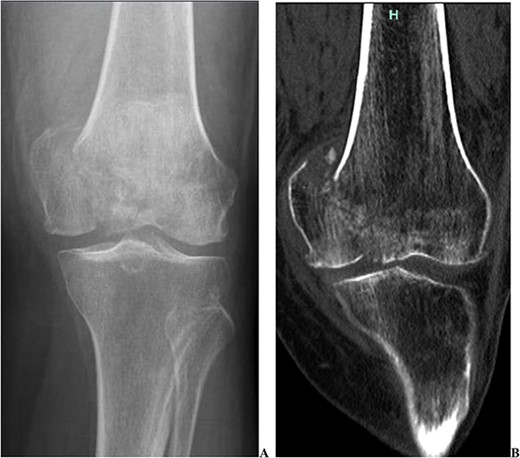

We present the case of a 76 year old Hispanic female previously managed for tri-compartmental osteoarthritis and lateral condyle insufficiency fracture of the left knee. She was being managed conservatively; however, the pain began to affect her well-being and activities of daily living (ADL). Most recently the patient suffered a mechanical ground level fall resulting in an ipsi-lateral medial condyle fracture as seen in Fig. 1. Single staged left knee medial condyle ORIF and CCK arthroplasty through a medial para-patellar approach was performed. The medial condyle fracture was reduced and stabilized using a 5-hole distal fibula locking plate in buttress mode. After fracture stabilization, a CCK arthroplasty was performed. Immediate post-operative imaging is seen in Fig. 2. Intra-operative photos are demonstrated in Fig. 3. The patient was made non-weight bearing for 2 weeks followed by weight bearing as tolerated (WBAT). An early weight bearing protocol was used given the majority of forces during ambulation would be placed through the total knee implant and not place significant stress on the medial condyle ORIF. At 3 months post-operatively, the patient obtained 0–120° range of motion (ROM) and was freely WBAT. At 8 weeks, however, the patient required a manipulation under anesthesia for regressing to 0–95° ROM. Figure 4 demonstrates intra-operative images of the manipulation. At 3 years follow up, her ROM was 5–95 with good strength without any further complication or subsequent procedures. Three years post-operatively the patient reported improved function with ADLs, significantly improved pain, and better mental health.

Two post-operative radiographs of the left knee demonstrating the constrained condylar knee arthroplasty, along with the open reduction internal fixation of the medial condyle using a distal fibula locking plate in buttress mode.